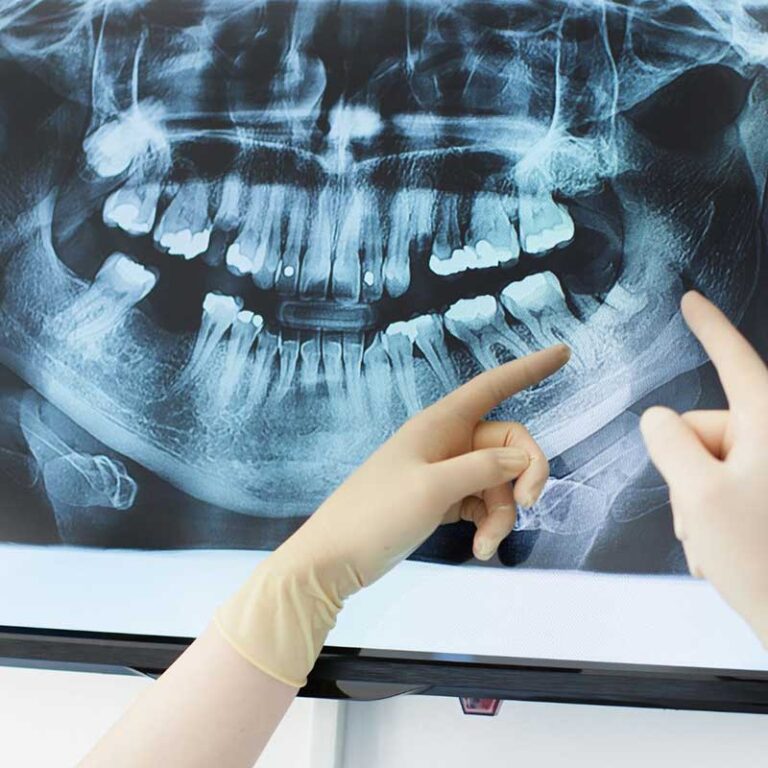

X-Rays and Imaging

Advanced imaging techniques, such as X-rays or CT scans, provide detailed views of the tooth’s position, root structure, and the condition of surrounding bone and tissues. These images are crucial for planning a precise and safe extraction.